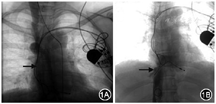

患者女,49岁,2019年4月10日因“双下肢及颜面部水肿,伴纳差、腹胀及乏力2年”入院。8年前患者因急性病毒性心肌炎并发阿斯综合征行心脏起搏器植入术,术后未取除起搏器。2019年4月因双下肢及面部浮肿等症状在外院行下腔静脉血管造影,提示上、下腔静脉狭窄;先后两次行球囊扩张效果不佳,住院期间心电图大致正常。入院检查:24 h动态心电图示正常窦性心律;腔静脉造影及静脉CT提示上腔静脉长狭窄、下腔静脉入右心房处环状狭窄,奇静脉侧支循环为主(图1);超声心动图提示下腔静脉近右心房处导线样回声伴静脉血流明显增快,静脉最大血流速率163 mm/s。